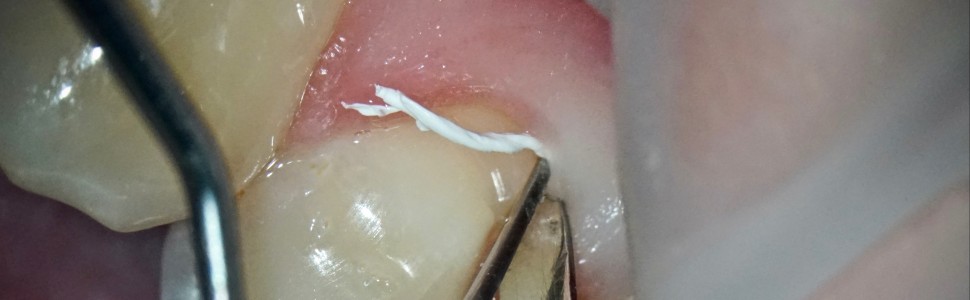

Niepróchnicowe ubytki tkanek twardych zębów w okolicy przyszyjkowej stanowią coraz częstszy problem, z jakim pojawiają się pacjenci w gabinecie stomatologicznym. Prezentowany cykl przybliża tematykę związaną z rekonstrukcją niepróchnicowych ubytków tkanek twardych zębów w okolicy przyszyjkowej z zastosowaniem materiałów kompozytowych. Niniejsza część jest poświęcona profilaktyce oraz możliwościom leczenia z uwzględnieniem roli izolacji z zastosowaniem koferdamu oraz dedykowanych technik adhezyjnych.

Non-carious cavities in the hard tissues of the teeth in the cervical area are an increasingly common problem faced by patients in the dentist’s office. This series of articles presents the issues related to the reconstruction of non-carious cavities in the hard tissues of the teeth in the cervical area with the use of composite materials. This part is devoted to prevention and treatment options taking into account the role of isolation with the cofferdam and dedicated adhesive techniques.